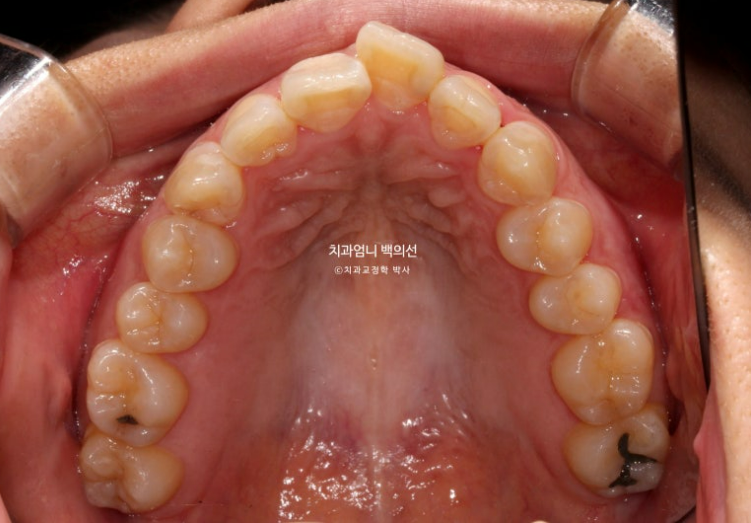

아래 앞니 사이에 벌어진 공간이 있고 위 앞니는 덧니가 있습니다.

앞니에 울퉁불퉁한 띠가 있는데 법랑질저형성증 입니다.

하지만 윗니 돌출도 있어서 상악 소구치 2개 발치교정 쪽으로 치료계획을 세웠습니다.

아래는 치아가 원래 2개가 없으니 상악만 교정발치 2개를 하면 균형도 맞아지고 상악에만 국한된 덧니와 돌출 문제도 같이 해결할 수 있습니다.

단 이경우 아래 송곳니는 결손된 앞니 자리로 끌어와 앞니로 대체하고 아래 작은어금니를 송곳니 자리로 끌어와 송곳니로 대체합니다.

중심선은 정확히 맞고 앞니 교합도 좋습니다.

어금니 교합관계는 정확히 1급입니다. 송곳니 자리에 있는 파란 화살표는 사실 송곳니가 아니라 첫번째 작은어금니입니다.

양측 어금니 교합관계는 기존 3급에서 1급으로 개선되었고